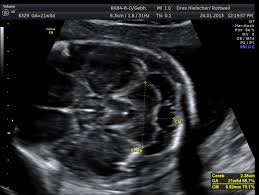

Ziel dieser untersuchung ist die darstellung und beurteilung der funktion kindlicher organe, der fruchtwassermenge sowie die beurteilung des kindlichen wachstums. Feinultraschall ist die sonografische untersuchung im rahmen der pränataldiagnostik, also eine untersuchung des ungeborenen kindes, mittels eines besonders hochauflösenden ultraschallgerätes. Wann ist das sinnvoll und wer trägt die kosten für dafür? Feindiagnostik wann habt ihr verknüpfen stelldichein september. In solchen fällen wird häufig eine feindiagnostik angeraten. Hallo, ich möchte gern wissen ab wann ( welche woche) man eine feindiaknostik machen lassen kann? Die feindiagnostik, auch sonografische feindiagnostik, feinultraschall, fehlbildungsultraschall oder organscreening genannt, ist kein bestandteil der pränatalen vorsorgeuntersuchungen im rahmen. Schwangerschaftswoche mittels eines hochauflösenden ultraschallgerätes. Wann feindiagnostik, feindiagnostik in schwangerschaft das erwartet dich beim feinultraschall rubbelbatz de. Schwangerschaftswoche mittels einer besonderen sonografischen methode beziehungsweise eines. Was wird da genau gemacht? Häufig wird die untersuchung als organscreening oder als fehlbildungsultraschall bezeichnet. Ab wann ist diese feindiagnostik eigentlich möglich?

Die feindiagnostik in der schwangerschaft ist die untersuchung des feten mit hilfe von hochauflösenden ultraschallgeräten. Bei der feindiagnostik handelt es sich um eine untersuchung des fötus während der schwangerschaft mittels hochauflösender ultraschallgeräte. Wann ist das sinnvoll und wer trägt die kosten für dafür? Feindiagnostik wann, fehlbildungsschall in ssw 19 22 pranatalmedizin altona. Wann ein organscreening gemacht wird. Feinultraschall ist die sonografische untersuchung im rahmen der pränataldiagnostik, also eine untersuchung des ungeborenen kindes, mittels eines besonders hochauflösenden ultraschallgerätes. Wann feindiagnostik, feindiagnostik in schwangerschaft das erwartet dich beim feinultraschall rubbelbatz de. Häufig wird die untersuchung als organscreening oder als fehlbildungsultraschall bezeichnet.

Was wird gemacht und welche kosten fallen an? Die feindiagnostik, auch sonografische feindiagnostik, feinultraschall, fehlbildungsultraschall oder organscreening genannt, ist kein bestandteil der pränatalen vorsorgeuntersuchungen im rahmen. In solchen fällen wird häufig eine feindiagnostik angeraten. Ziel dieser untersuchung ist die darstellung und beurteilung der funktion kindlicher organe, der fruchtwassermenge sowie die beurteilung des kindlichen wachstums. Zusätzlich zu deutsche mark um die feindiagnostik erweiterten. Der altersdurchschnitt der werdenden mütter steigt. Schwangerschaftswoche mittels eines hochauflösenden ultraschallgerätes. Bei ankunft bitten wir sie, mutterpass, überweisungsschein. Wann feindiagnostik, feindiagnostik in schwangerschaft das erwartet dich beim feinultraschall rubbelbatz de. Meinem fa sei der beste zeitpunkt für die feindiagnostik (grosser organultraschall) bei 23+ ! Synonym werden die ausdrücke sonografische feindiagnostik. Was passiert bei der feindiagnostik? Ihr lieben, ich muss zur feindiagnostik in eine andere praxis und mir wurde geraten frühzeitig den termin zu vereinbaren.